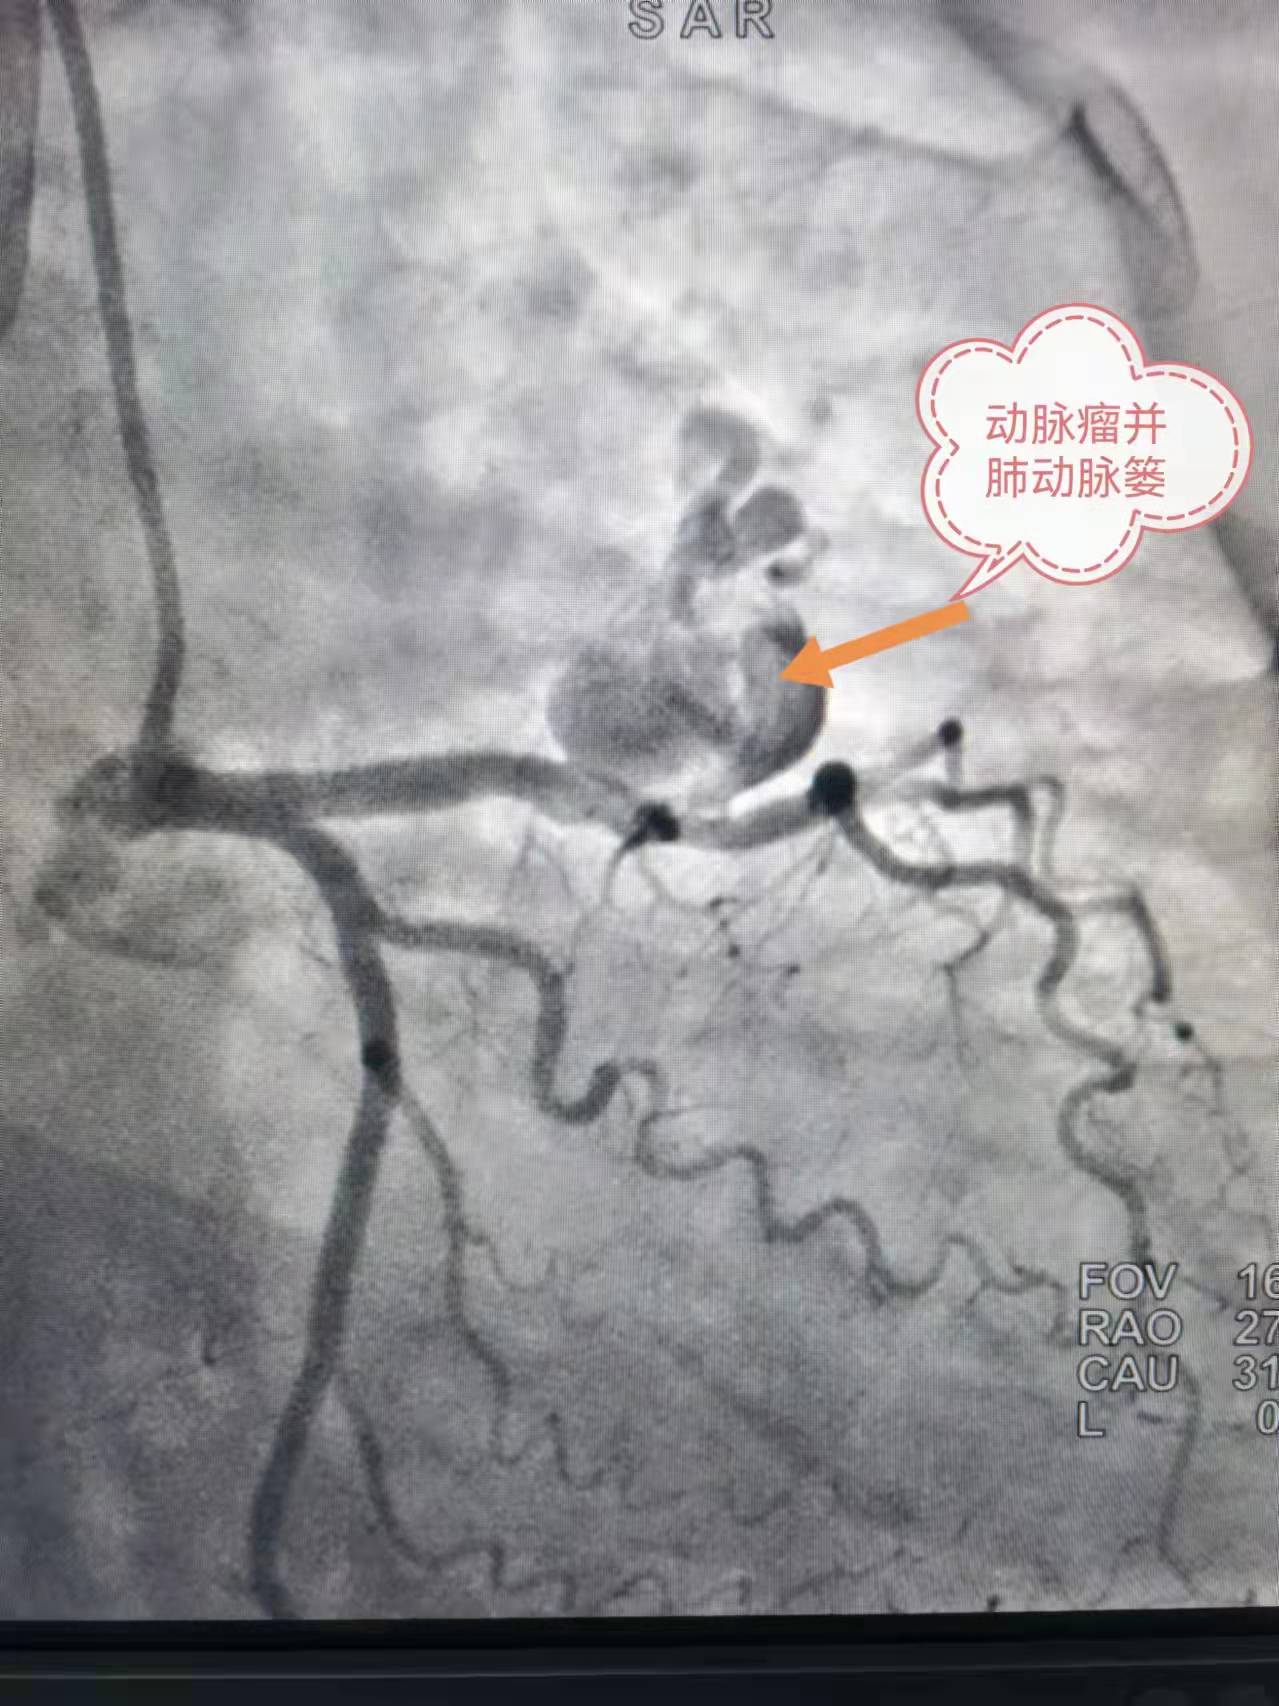

术前造影

57 岁的陶女士四年前反复出现胸背部阵发性胀痛,以夜间平躺时居多,开始未予重视。直到一个月前,上述症状加重,并伴有气短,在当地医院进一步检查后,确诊为巨大冠状动脉瘤伴肺动脉瘘。辗转多家医院就诊,均因病情复杂、手术风险大,被告知只能开胸手术。后经人介绍来到湖南省人民医院岳麓山院区胸痛中心就诊。

胸痛中心主任欧柏青教授对患者进行充分评估,考虑其除巨大冠状动脉瘤,还合并肺动脉瘘,病情复杂,立即开展MDT(多学科诊疗)讨论,邀请心内科潘宏伟教授、介入血管外科向斌主任反复评估患者病情,研究造影影像,讨论并制定了严谨周密的手术方案。